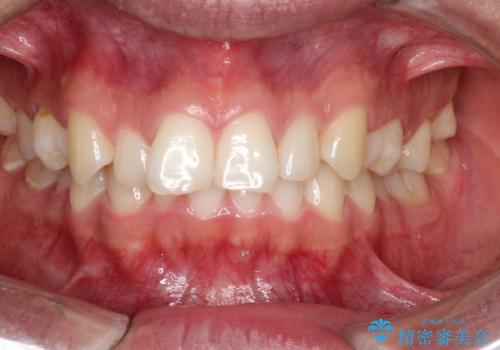

- 咬み合わせの不調和と歯並びのデコボコを主訴にご来院された患者様です。

精密矯正検査の結果、歯を抜かずに非抜歯でワイヤー矯正で治療を行う方針としました。

叢生(歯のデコボコ)の量が多く、加えてディープバイト(過蓋咬合)や重度の捻転も認められたため、リンガルアーチやマイクロインプラントなどの補助装置を併用し、治療を進めました。